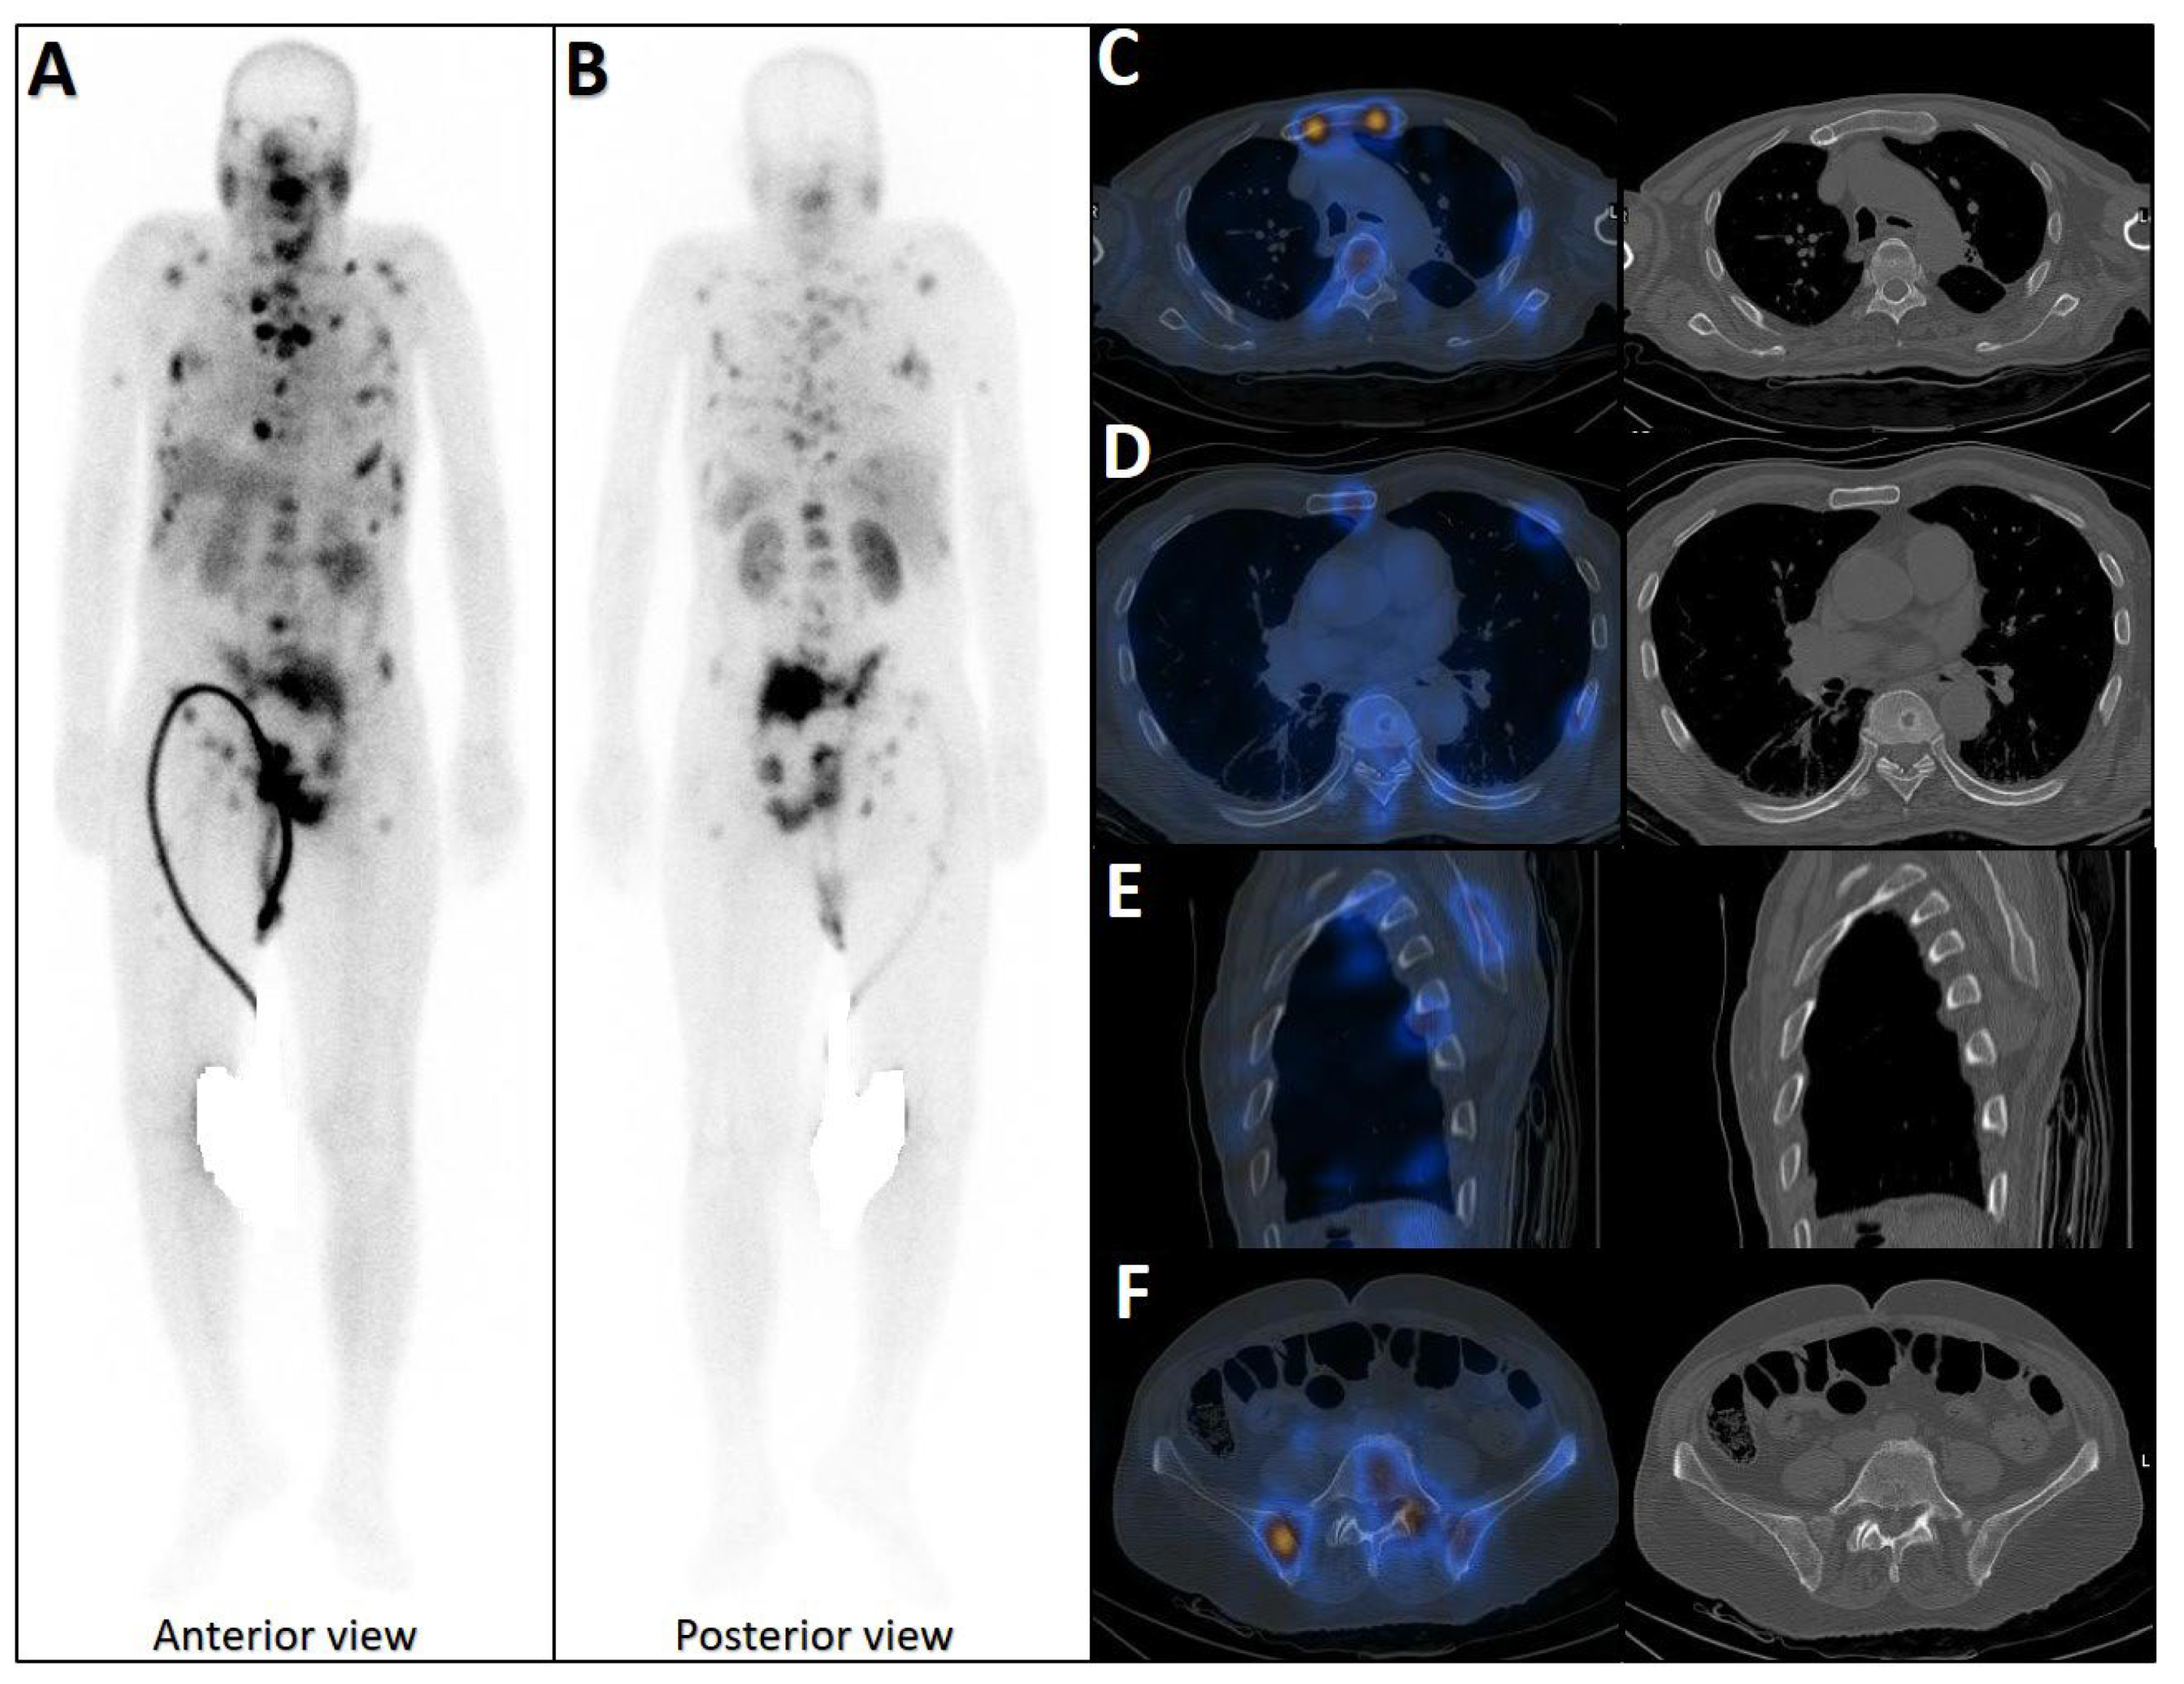

Figure 6.

Complete discordant findings between PSMA and bone scan. 61-year-old male referred for staging that transrectal ultrasound-guided prostate biopsy showed GS 4 + 3 (12 of 12 cores involved), perineural invasion (+), and serum PSA level = 17 ng/mL. A whole-body bone scan revealed multiple increased tracer uptake in bilateral rib (A). 99mTc-PSMA SPECT/CT revealed no abnormal tracer uptake (B). Considering discordant findings in the 99mTc-PSMA and bone scan, the referring physician decided to request a 68Ga-PSMA PET/CT. The scan showed (C) multiple foci of increased activity in the left side of the prostate gland (D) as well as two foci of increased activity in bilateral ribs with no density changes on the corresponding CT images (SUVmax up to 3.84) (blue arrowhead, E,F). The rib lesions were finally considered as equivocal. Ultimately, the patient underwent RP and nadir PSA was 0.02 ng/mL.